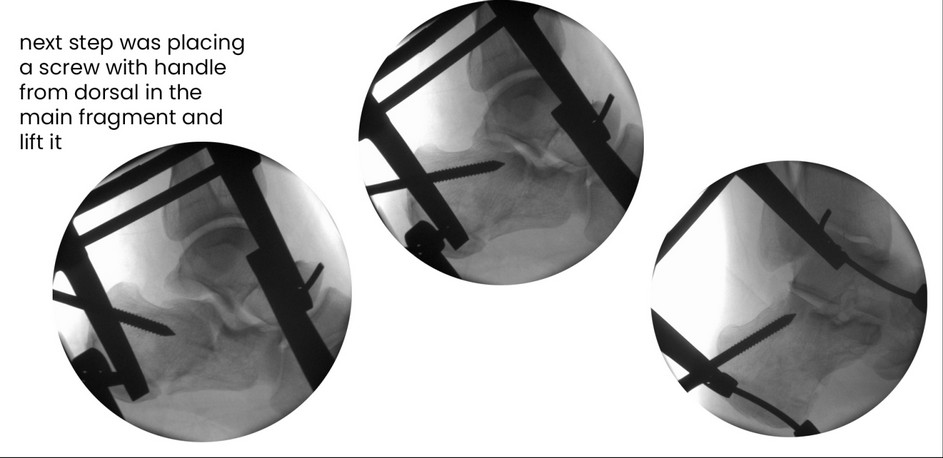

back Case 18SF, male 42 years , tonque-type right, depression-type left, surgery one day after trauma, show you surgery on right side, reduction in combination extension and after Westhues